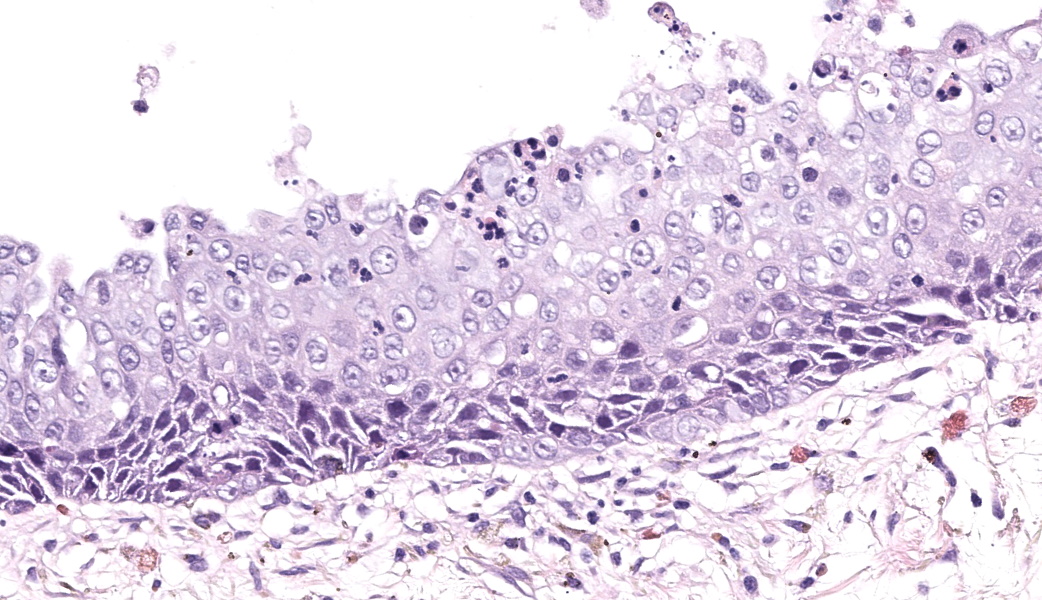

Eye: Overlying the corneal endothelium, anterior and posterior iris, portions of the lens epithelium, and the inner surface of the retina, as well as effacing and replacing the ciliary body, and occluding the drainage angle is an unencapsulated, densely cellular, infiltrative, neoplasm composed of epithelial cells arranged in broad dense cords on a moderate fibrovascular stroma. Neoplastic cells are polygonal with distinct cell borders, pronounced intercellular bridging, a moderate amount of pale eosinophilic cytoplasm, and irregularly round to vesiculate nuclei, with up to three distinct nucleoli. Anisocytosis and anisokaryosis is moderate. The mitotic rate is high with up to 12 mitotic figures per ten 40x HPF. Multifocally, neoplastic cells exhibit squamous differentiation. Near the optic nerve, the neoplastic cells invade the vascular and fibrous tunics, elevating and dissecting beneath the retinal pigment epithelium under a detached and coiled degenerate retina. At the caudal interior surface of the globe, there are numerous neutrophils admixed with abundant eosinophilic cellular and karyorrhectic debris and neoplastic cells infiltrate into the retinal vasculature.Contributor's Morphologic Diagnoses:

This case contributor gives a thorough review of intraocular neoplasms in cats, touching on many major points of discussion during review of this case. Conference participants were readily able to reach a diagnosis of metastatic carcinoma, but not all were convinced that this was a metastatic squamous cell carcinoma (SCC) due to the lack of dyskeratosis within neoplastic epithelial cells, coupled with the lack of a primary mass found during workup. The prominent intercellular bridging between the neoplastic cells was noted by all, which can be a major feature of SCC; and squamous cell carcinomas are common tumors of the feline head; however other participants felt strongly that they could not rule out a carcinoma of other origin based on histology alone. For this reason, a morphologic diagnosis of “metastatic carcinoma” was ultimately favored by participants in this case due to the lack of clear-cut evidence of a squamous cell carcinoma on the H&E.There was no argument to be found on whether this was primary or metastatic, as the histologic evidence was strongly supportive of a metastatic process (i.e., the neoplasm primarily found within the highly vascular choroid and uvea, intravascular neoplastic cell emboli, etc.). The secondary changes in the eye were also discussed and it was concluded that this eye had glaucoma secondary to the neoplasm, evidenced by the retinal ganglion cell degeneration and loss with tapetal sparing, occlusion of the drainage angles by both the neoplasm and inflammation, buphthalmia (enlarged globe, attenuated and degenerative corneal epithelium, scleral thinning), and perivascular edema of the aqueous veins that drain the trabecular meshwork of the drainage angle.